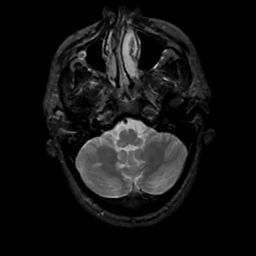

MR Study #15, June 9, 1991 -- Slice #9